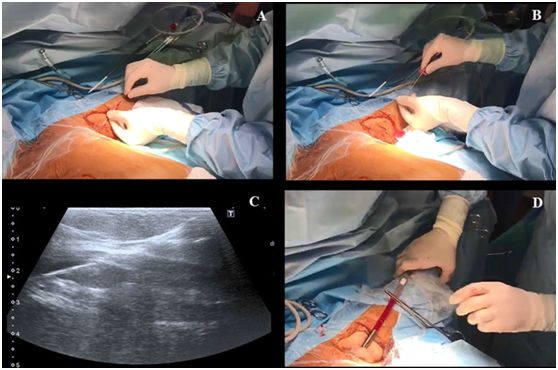

第三步,操作者左手持超声探头,右手持带穿刺针的注射器在超声引导下对腋静脉进行穿刺,超声长轴图像平面内同时可见静脉腔及穿刺针(图2)。皮肤穿刺点尽可能靠近超声探头远端的短边上。当穿刺针触碰到静脉前壁时,在压力的作用下,静脉壁会出现下沉塌陷,因此,此时应快速进针。

当在腋静脉腔内视察到针尖的斜面时(一个白点),可以很容易地确定穿刺针在血管内的位置(图2C)。也可以通过回抽血液1-2ml来确认穿刺针的位置是在静脉内。当患者血压较低时,无搏动性血流出现并不能排除穿刺到动脉的可能。随后置J形导丝,导丝的位置也可能在超声实时下确认(图3,A-C)。也可以通过颈部超声探查来排除导丝进行左侧颈内静脉。导丝置入长度应限定在20cm,以避免引起心律失常。随后扩张皮肤穿刺点,用Seldinger技术置入导管。在输注任何液体之前,回抽确认导管远端是否在血管腔内,随后再用肝素盐水冲洗导管。导管置入深度为20cm。

图2,A 沿超声探头长轴插入穿刺针;B 超声视窗下可见穿刺针进行静脉;C 超声视窗下看到的血管内穿刺针斜面。

图3,A和B置入导丝,C超声视窗下可见静脉的导丝;D 把导管固定